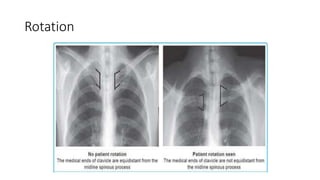

A normal chest x-ray shows the lungs, heart, bones, and soft tissues appearing healthy and unobstructed. The document discusses the different views used in chest x-rays, including PA, AP, lateral, and lateral decubitus views. It also covers topics like depth of inspiration, rotation exposure, the lobes of the lungs, identifying the heart, and how to read a normal chest x-ray.